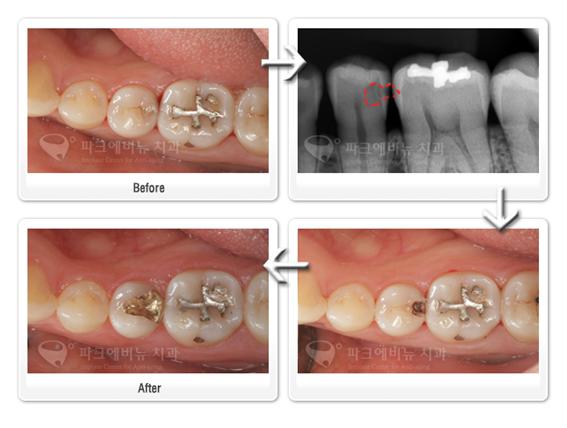

기존 아말감 부위가 너무 넓거나 옆면까지 연결이 되어있는 경우에는 아래 사진처럼 금으로 때우는 것이 깨질 위험도 줄어들고 좀 더 튼튼하게 사용할 수 있습니다.

오래된 아말감 치료 - 금 인레이 치료

오래된 아말감 치료 – 금 인레이 치료